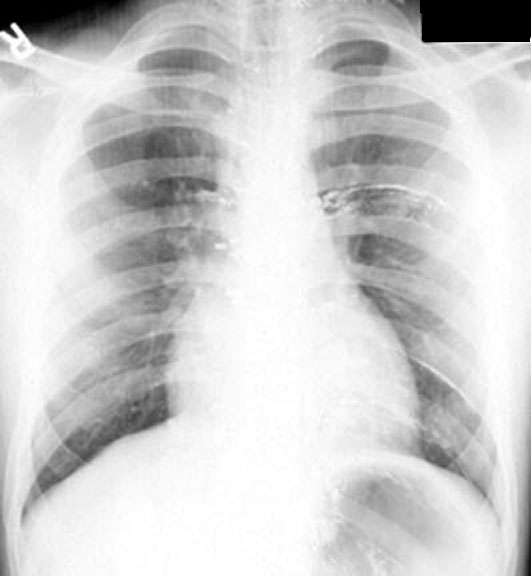

Extravasated Myelogram Dye

• Dye along rib margins